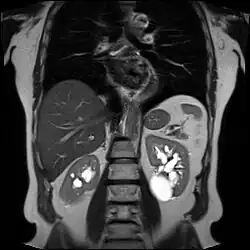

Numerous renal cysts are seen in the cystic kidney diseases, which include polycystic kidney disease and medullary sponge kidney.

Advanced polycystic kidney disease with multiple cysts.[13] -